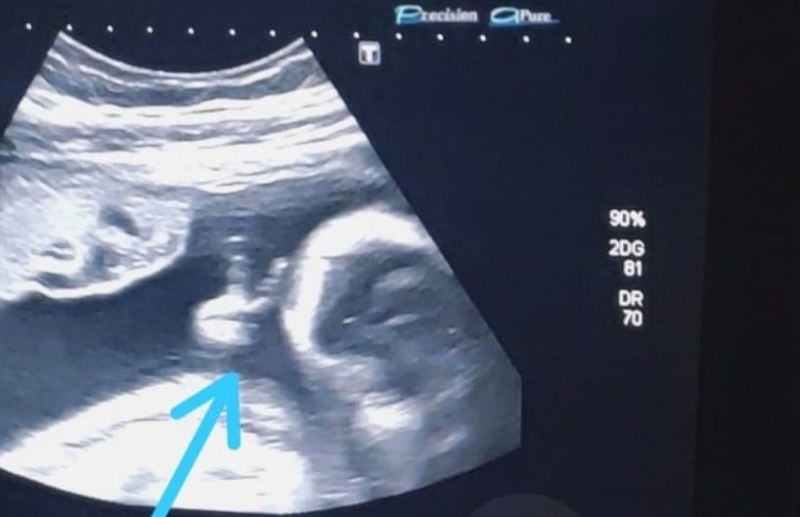

Mas, desta vez, ele se deparou com a surpresa de ver o filho, que se chamará Davi, fazendo um sinal de 'V' com uma das mãozinhas.

“Até a médica falou: 'olha, ele fez o sinalzinho de vitória com a mão'. Eu fiquei sem acreditar”, afirma. Ele encara a situação como um sinal divino de que vai conseguir superar o tratamento e vencer a doença.